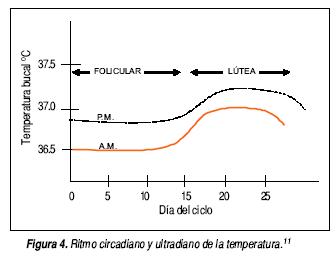

Éste es un capítulo un tanto olvidado, pues lo más que se suele investigar es la magnitud, el horario y los síntomas que la preceden y la suceden. Con excepción de la llamada hiperpirexia (un aumento muy elevado de la temperatura que suele ocurrir más en la hipertermia que en la fiebre), la magnitud tiene poco valor semiológico. El que una fiebre se preceda de escalofrío y se siga de sudación tampoco ayuda a identificar su causa, puesto que en mayor o menor medida todas las fiebres son así; la magnitud del escalofrío se asocia con la rapidez con que asciende la temperatura y la de la sudación con la velocidad con que desciende. Que la fiebre sea de predominio vespertino tampoco ayuda a descubrir su origen puesto que también todas suelen ser así. La temperatura corporal (y toda la fase aguda)10 tiene un ritmo circadiano (e incluso uno ultradiano) que suele conservarse en la mayor parte de los casos de fiebre (Figura 4).11 Acaso, puede tener algún significado diagnóstico el que la fiebre sea de predominio matutino (lo que se ha llamado tifus inversus) que ocurre en casos de síndrome de supuración pulmonar porque durante la noche se acumulan las secreciones infectadas que empiezan a drenar con la tos matutina. La curva térmica ha dejado de tener valor semiológico, particularmente porque suele estar modificada con los tratamientos prescritos o autoprescritos. Sin embargo, hay dos tipos de curva que aún ayudan en el diagnóstico: la llamada fiebre recurrente (días con fiebre y días sin fiebre) que ocurre en algunas formas de paludismo, en borreliosis y en linfoma (fiebre de Pel-Ebstein) y, por otro lado, la fiebre en agujas, séptica o héctica que tiende a asociarse con procesos supurativos. No es necesario graficar la temperatura para poder identificar estos dos tipos de fiebre puesto que el interrogatorio puede descubrirla.